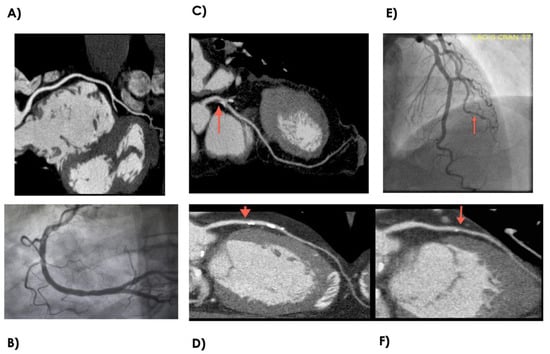

2.2. Coronary CTA